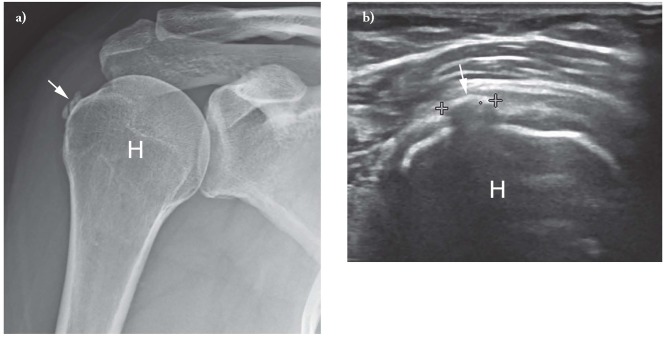

X quang

Với bệnh viêm gân vôi hóa chóp xoay, X quang thường quy có thể phát hiện vôi hóa ở các mô mềm xung quanh xương cánh tay và khoang dưới mỏm cùng vai, từ đó xác định nghi ngờ lâm sàng. X quang cũng có thể phát hiện sự hiện diện của vôi hóa ở những bệnh nhân thực hiện chụp x quang vì những lý do khác.

Siêu âm

- Trên siêu âm, cặn canxi thường xuất hiện tăng âm có hoặc không có bóng âm phía sau.

- Bianchi và Martinoli đã mô tả ba loại vôi hóa khác nhau, dựa trên tỷ lệ canxi khác nhau của chúng.

- loại I, vôi hóa xuất hiện dưới dạng các ổ tăng âm với bóng âm được xác định rõ do hàm lượng canxi khá cao.

- loại II, vôi hóa xuất hiện dưới dạng các ổ tăng âm với bóng âm nhẹ do lượng canxi giảm;

- loại III, vôi hóa xuất hiện gần như đồng âm với gân, không có bóng âm và thường khó chẩn đoán

- Loại I tương ứng với giai đoạn hình thành trong khi vôi hóa loại II và III tương ứng với giai đoạn hấp thu.